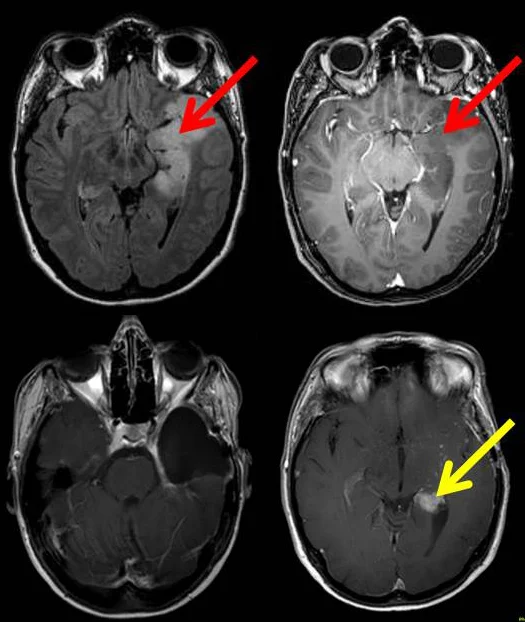

Bilder des Gehirns einer Patientin mit einem Gliom Zurück